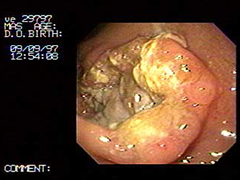

Paciente Masculino de 51 Años:

Hermano de prestigioso Cirujano Pediatra de El Salvador. El cual me solicita que le practique este estudio, le diagnosticamos este carcinoma obstructivo, la imagen endoscópica de control, Fue después de un año de habérsele diagnosticado por lo que Se le había practicado una derivación en omhmeda por haber sido irresecable al intento quirúrgico es de notar que esta imagen endoscópica es después de haber recibido quimioterapia y radiaciones con Cobalto.